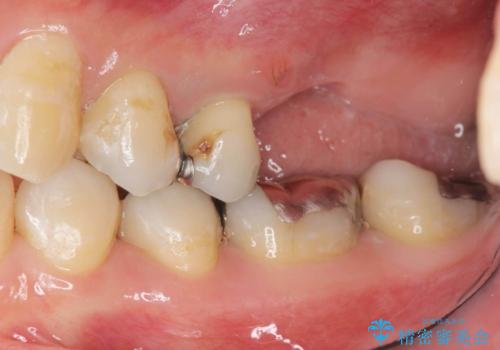

上顎奥歯のインプラント治療

- 奥歯を失い咬合機能の回復のためインプラント治療を希望され来院されました。

奥歯を2本失うと、他の歯の負担が増加し残っている歯の状態が悪くなるリスクがあります。

しっかりと咬合機能の回復できるインプラント治療を計画します。

しっかりと食事ができるようになり、当院のインプラント治療に満足いただくことができました。